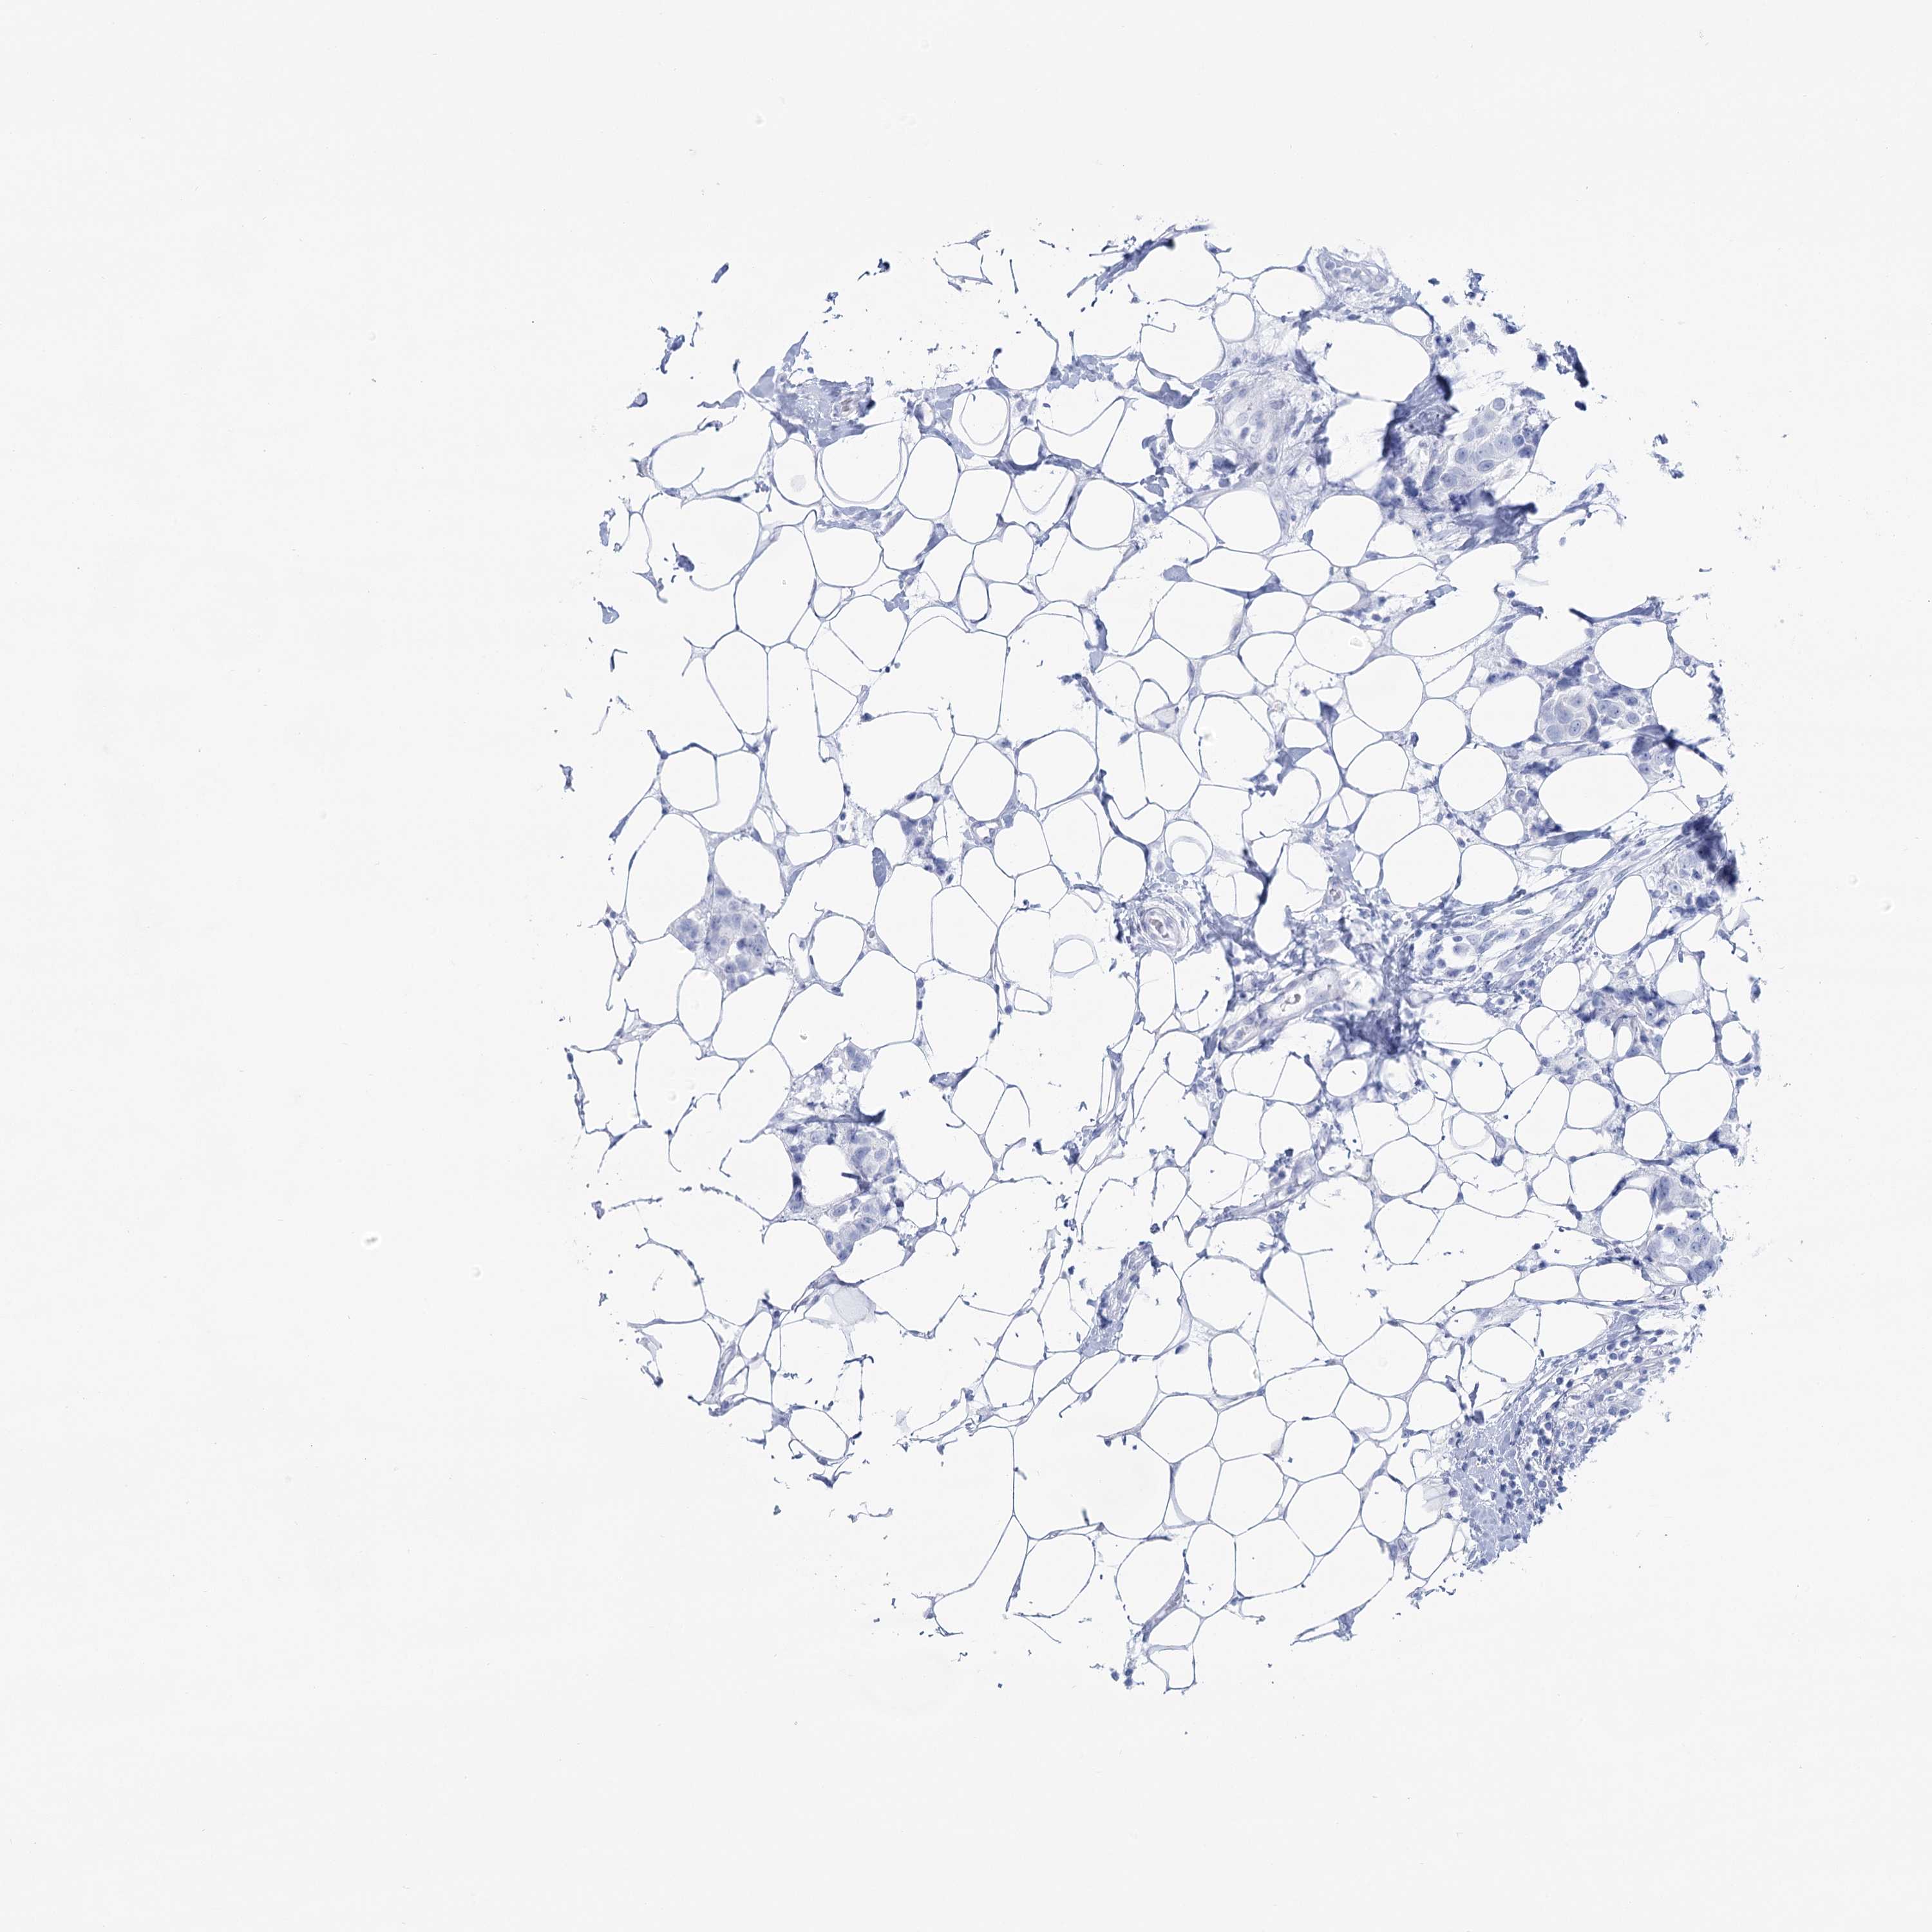

Breast cancer

Human cancer